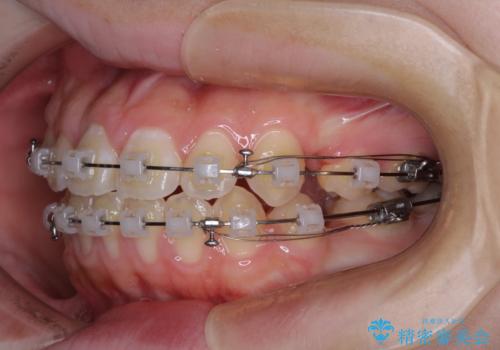

- クリアブラケット

上下左右の第一小臼歯4本を抜歯し、ワイヤー装置での抜歯矯正を行っていくのですが、原因である舌の突出癖を改善しないことには治療がうまく進められないため、舌のトレーニングを徹底するよう指導していくこととしました。

当初は舌のトレーニングがうまくできていなかったのですが、途中から奏効し、非常に短い期間で治療を終えることができました。